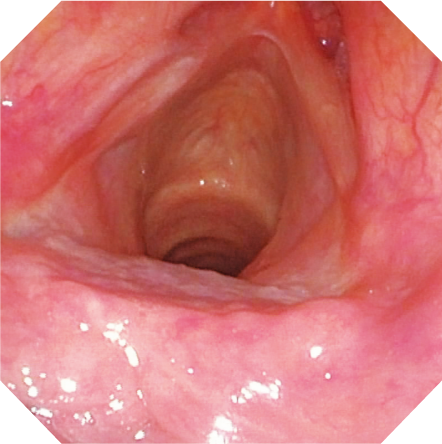

CCD の高密度化により、HD 対応を実現したビデオスコープENF-VH。これまで以上に微細な観察をサポートします。

通常光

NBI